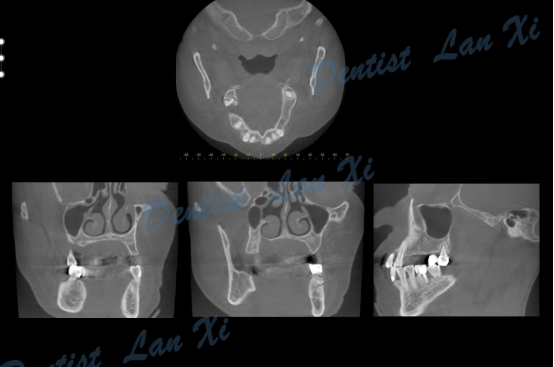

第一步:数据采集(口扫或仓扫+CBCT

第二步:数据匹配

(CBCT采集的Dicom数据与口扫获取的STL数据进行匹配,通过牙齿位点进行匹配。)

在数字化种植导板下,通过CBCT、口扫等途径获取口腔三维信息内容。使患者在种植之前就可以了解到种植方案的相关细节,清晰地看到牙齿修复之后的模拟展示图,提前预知种植术后的效果。

二、精准控制 更安全

在数字化种植导板下的外科手术更加精准。种植体植入方向、位置、角度、深度等一目了然,即可将种植体精准植入到最佳位置,获得更优异的临床效果,手术安全性更高。